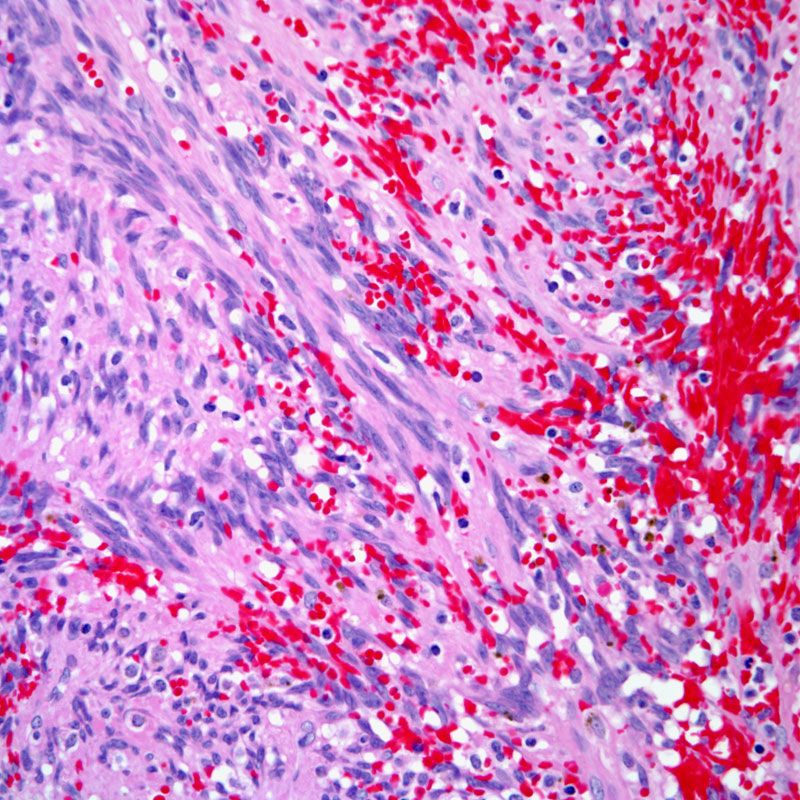

Lymphoma

A cancer of the lymphatic system of the body involving immune cells.

Can babies get lymphoma?

Lymphomas, both non-Hodgkin and Hodgkin lymphoma, are the third most common cancer in children. Non-Hodgkin lymphoma in children (NHL) can occur at any time during life, but is most common in younger children. Hodgkin lymphoma is more common in adolescents. There is no known cause of lymphoma in children.

What are the signs of lymphoma in a child?

Common symptoms include:Enlarged lymph nodes (seen or felt as lumps under the skin)Abdominal (belly) swelling or pain.Feeling full after eating only a small amount of food.Shortness of breath, wheezing, or cough.Fever.Weight loss.Night sweats.Fatigue (feeling very tired)

What are the signs of lymphoma in a child?

Common symptoms include:Enlarged lymph nodes (seen or felt as lumps under the skin)Abdominal (belly) swelling or pain.Feeling full after eating only a small amount of food.Shortness of breath, wheezing, or cough.Fever.Weight loss.Night sweats.Fatigue (feeling very tired)

What are the signs that you have a cancerous lymph node?

SymptomsPainless swelling of lymph nodes in your neck, armpits or groin.Persistent fatigue.Fever.Night sweats.Shortness of breath.Unexplained weight loss.Itchy skin.

What does it mean when your lymph nodes are hard?

When lymph nodes are very hard instead of rubbery, this may indicate a more serious illness such as lymphoma or leukemia.